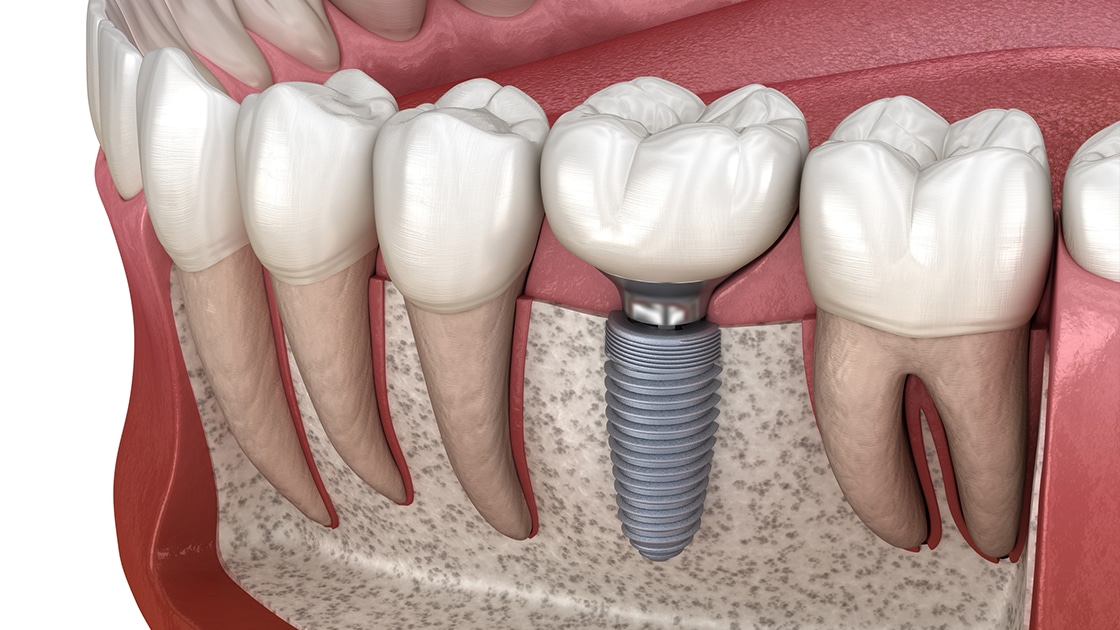

Implant Dentar

Implanturi titanium de cea mai înaltă calitate pentru înlocuirea dinților lipsă.